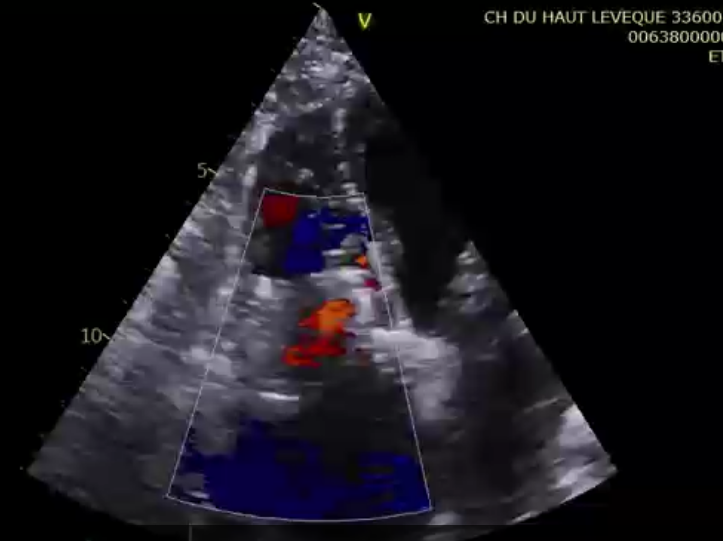

術(shù)后超聲提示微量瓣周漏